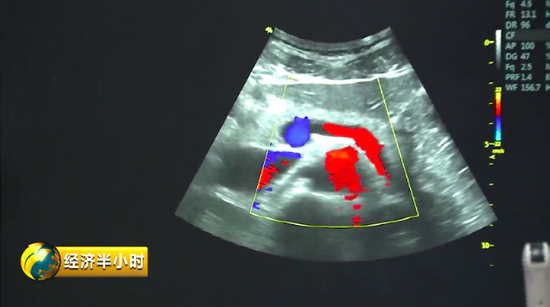

“彩超”,人们并不陌生,但是既能诊断又能帮助治疗的“彩超”对大多数人来说却是陌生的。

有一个特殊的彩色B超设备,不仅能够精确诊断,还能帮助大夫有效地给予患者治疗。也就是说,在治疗疾病时,在超声波的介入下,药物被精准送达病变位置,释放药物,从而实现靶向治疗。而且这个彩色B超设备副作用很少,安全性特别好。《经济半小时》记者在苏州工业园区了解到,目前这种彩色B超设备在国际上已经达到一流水平。

显示速率越快,意味着成像效果越好,医生的诊断和治疗也会更精确。公司研发总监高文友告诉记者,他们一代数据处理平台的速度可以理解成 5G 速度的 10 倍,而目前开发出来的二代产品,传输带宽比上一代高了将近150倍;成像显示的速率,也将近快了一百倍以上。